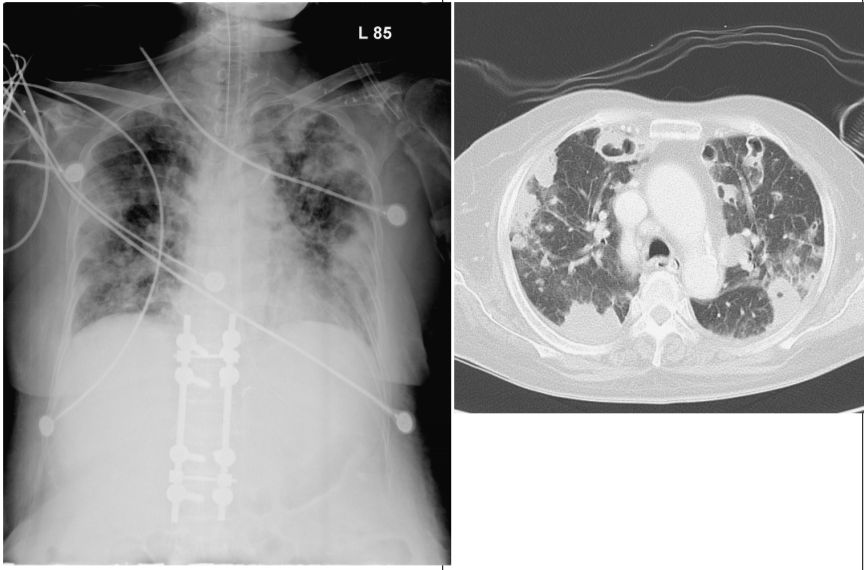

4. 肺功能檢查的氣流容積關係(flow-volume volume/loop)與疾病的配對(如圖),下列何者正確:(X軸為容積,Y軸為氣流,Y軸正向為吐氣、負向為吸氣, TLC:total lung capacity, RV: residual volume)

(A) 聲帶麻痺(vocal cord paralysis),造成呼吸道阻塞(variable extra-thoracic obstruction)。 (B) 復發性多軟骨炎(relapsing polychondritis),造成呼吸道阻塞(variable intra-thoracic obstruction)。 (C) 慢性阻塞性肺病(chronic obstructive pulmonary disease, COPD)造成的阻塞性通氣障礙(obstructive ventilatory impairment)。 (D) 肺纖維化(pulmonary fibrosis)造成的侷限性通氣障礙(restrictive ventilatory impairment)。 (E) 以上皆正確